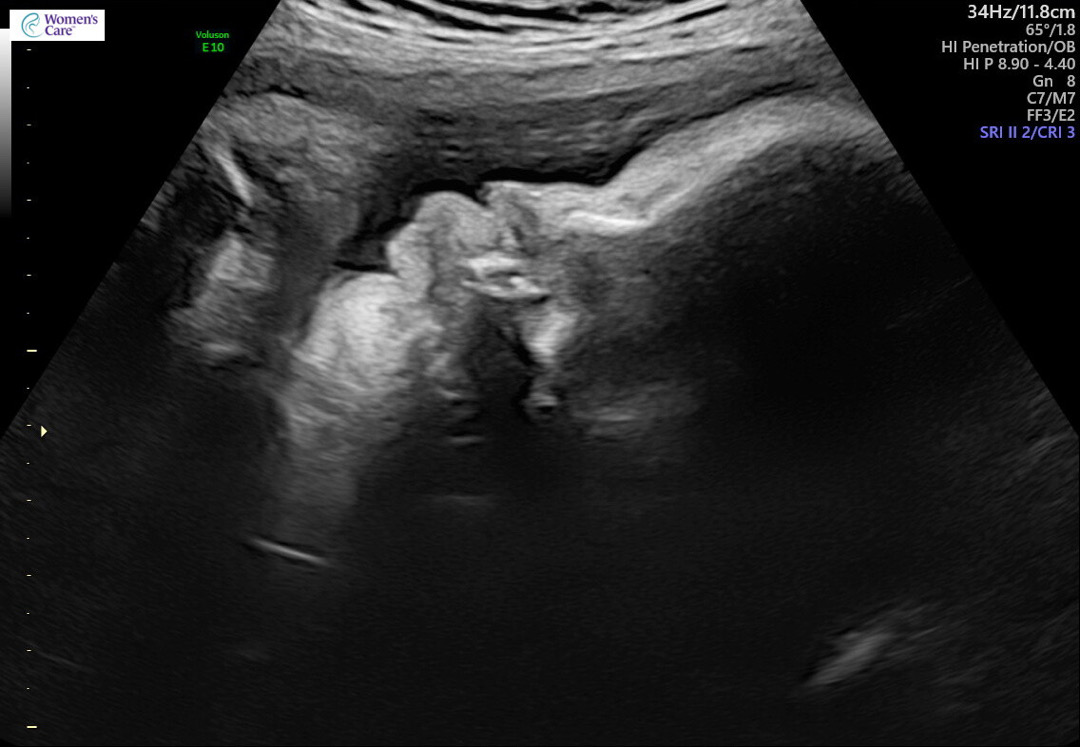

33주 초음파찍었는데요 가운데가 납작눌린 이명박..? 같은 코인데 다른사진은 또 안그렇긴하는데 괜찮은걸까요..? 각도에따라 이렇게 찌부되게보이기도하나여..?